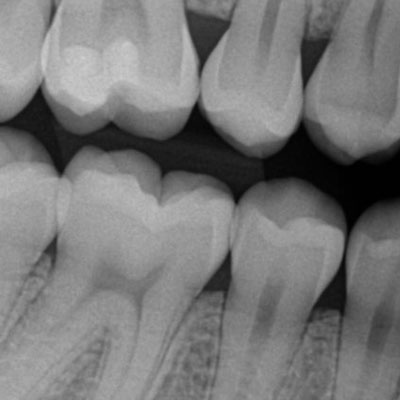

O exame radiográfico periapical proporciona ao dentista a visualização do dente em toda sua extensão, desde a coroa ao ápice, o espaço periodontal e o tecido ósseo.

A radiografia periapical ou RX periapical é um exame utilizado para mostrar radiograficamente a anatomia de um ou mais dentes (desde a coroa ao final da raiz), assim como as estruturas anatômicas vizinhas, ou seja, que estão ao redor dos dentes.

Esta radiografia pode ser usada para estudar qualquer dente (molar, pré-molar, e incisive os caninos) seja na arcada dentária superior ou na inferior para fins de diagnóstico e tratamento.